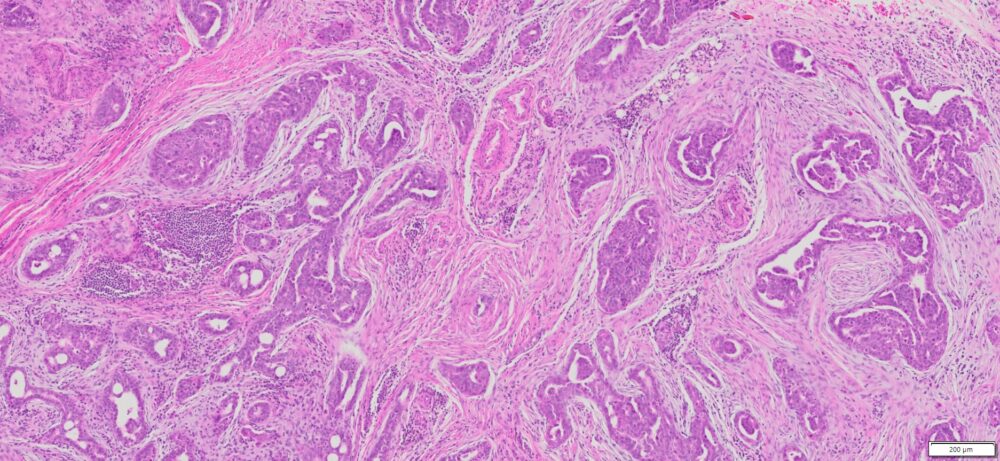

Description

| Tissue | Pathology Diagnosis | Gender/ Age (year) | %Tumor Area | Tumor Grade | TMN/Stage | IHC data |

| Omentum | Human omental high grade serous Carcinoma | Female/67 | 40% | III | NA | MOC-31(+),BER-EP4(+),P53(+), P16(+) |